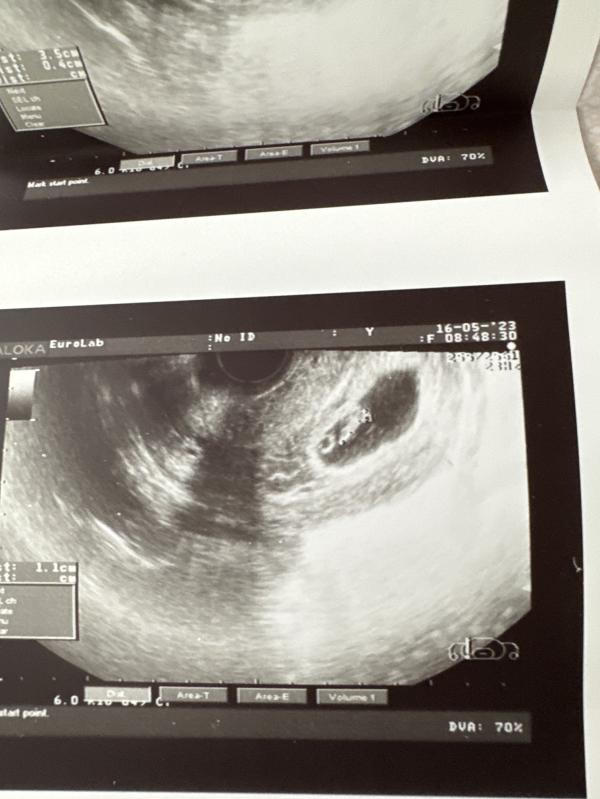

срок нам поставили на пару дней меньше 7.2 вместо 7.5

чсс 156